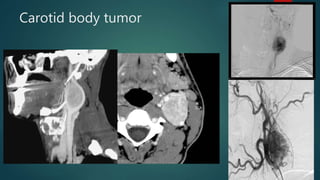

Carotid body tumor